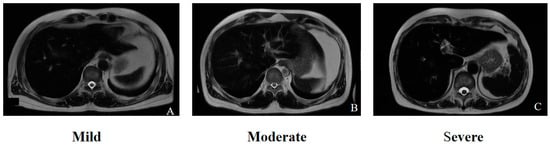

2.2.1. Liver-to-Muscle Signal Intensity Ratio (SIR)

- Gandon, Y.; Olivié, D.; Guyader, D.; Aubé, C.; Oberti, F.; Sebille, V.; Deugnier, Y. Non-invasive assessment of hepatic iron stores by MRI. Lancet 2004, 363, 357–362. [Google Scholar] [CrossRef]